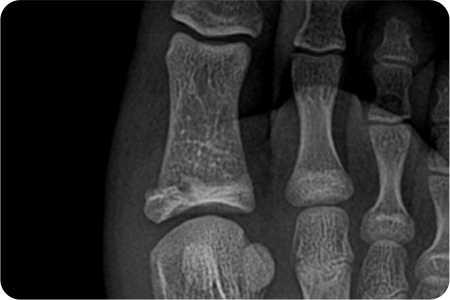

상지골절

• 위팔 골절, 쇄골 골절, 손목 골절은 손을 짚으면서 넘어질 때,

팔을 곧게 뻗은 채로 넘어질 때나, 교통사고, 타박 등에 의해 발생합니다.

골다공증 등으로 인해 뼈가 약해진 분에게 더 쉽게 발생할 수 있습니다.

• 골절이 발생한 부위 주변으로 통증과 압통이 발생하는데,

이 통증은 근육의 경직, 뼛조각의 겹침, 주위 연부 조직의 손상이 원인입니다.

골절 부위가 붓고, 피부 바깥에 보이는 점상 출혈이 발생합니다.

• 골절이 조금이라도 의심된다면 반드시 X-ray 촬영을 시행하여 확인해야 합니다.

부위별로 방향과 각도를 달리하여 여러 장의 X-ray를 찍어서 골절 유무를 확인합니다.